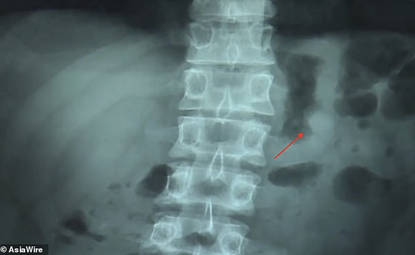

अस्पताल में जाकर यूजर ने x-ray करवाया जिसकी रिपोर्ट में साफ आ गया कि बेन के पेट में AirPod फंसा हुआ था। हालात को समझते हुए सर्जन ने बेन को समझाया कि उसके पेट की सर्जरी करके ही AirPod को बाहर निकाला जाएगा। लेकिन सर्जरी से पहले सर्जन ने सुझाया कि पहले प्राकृतिक तरीके से यानि शौच के जरिये इस AirPod को बाहर निकालने की कोशिश करेंगे।